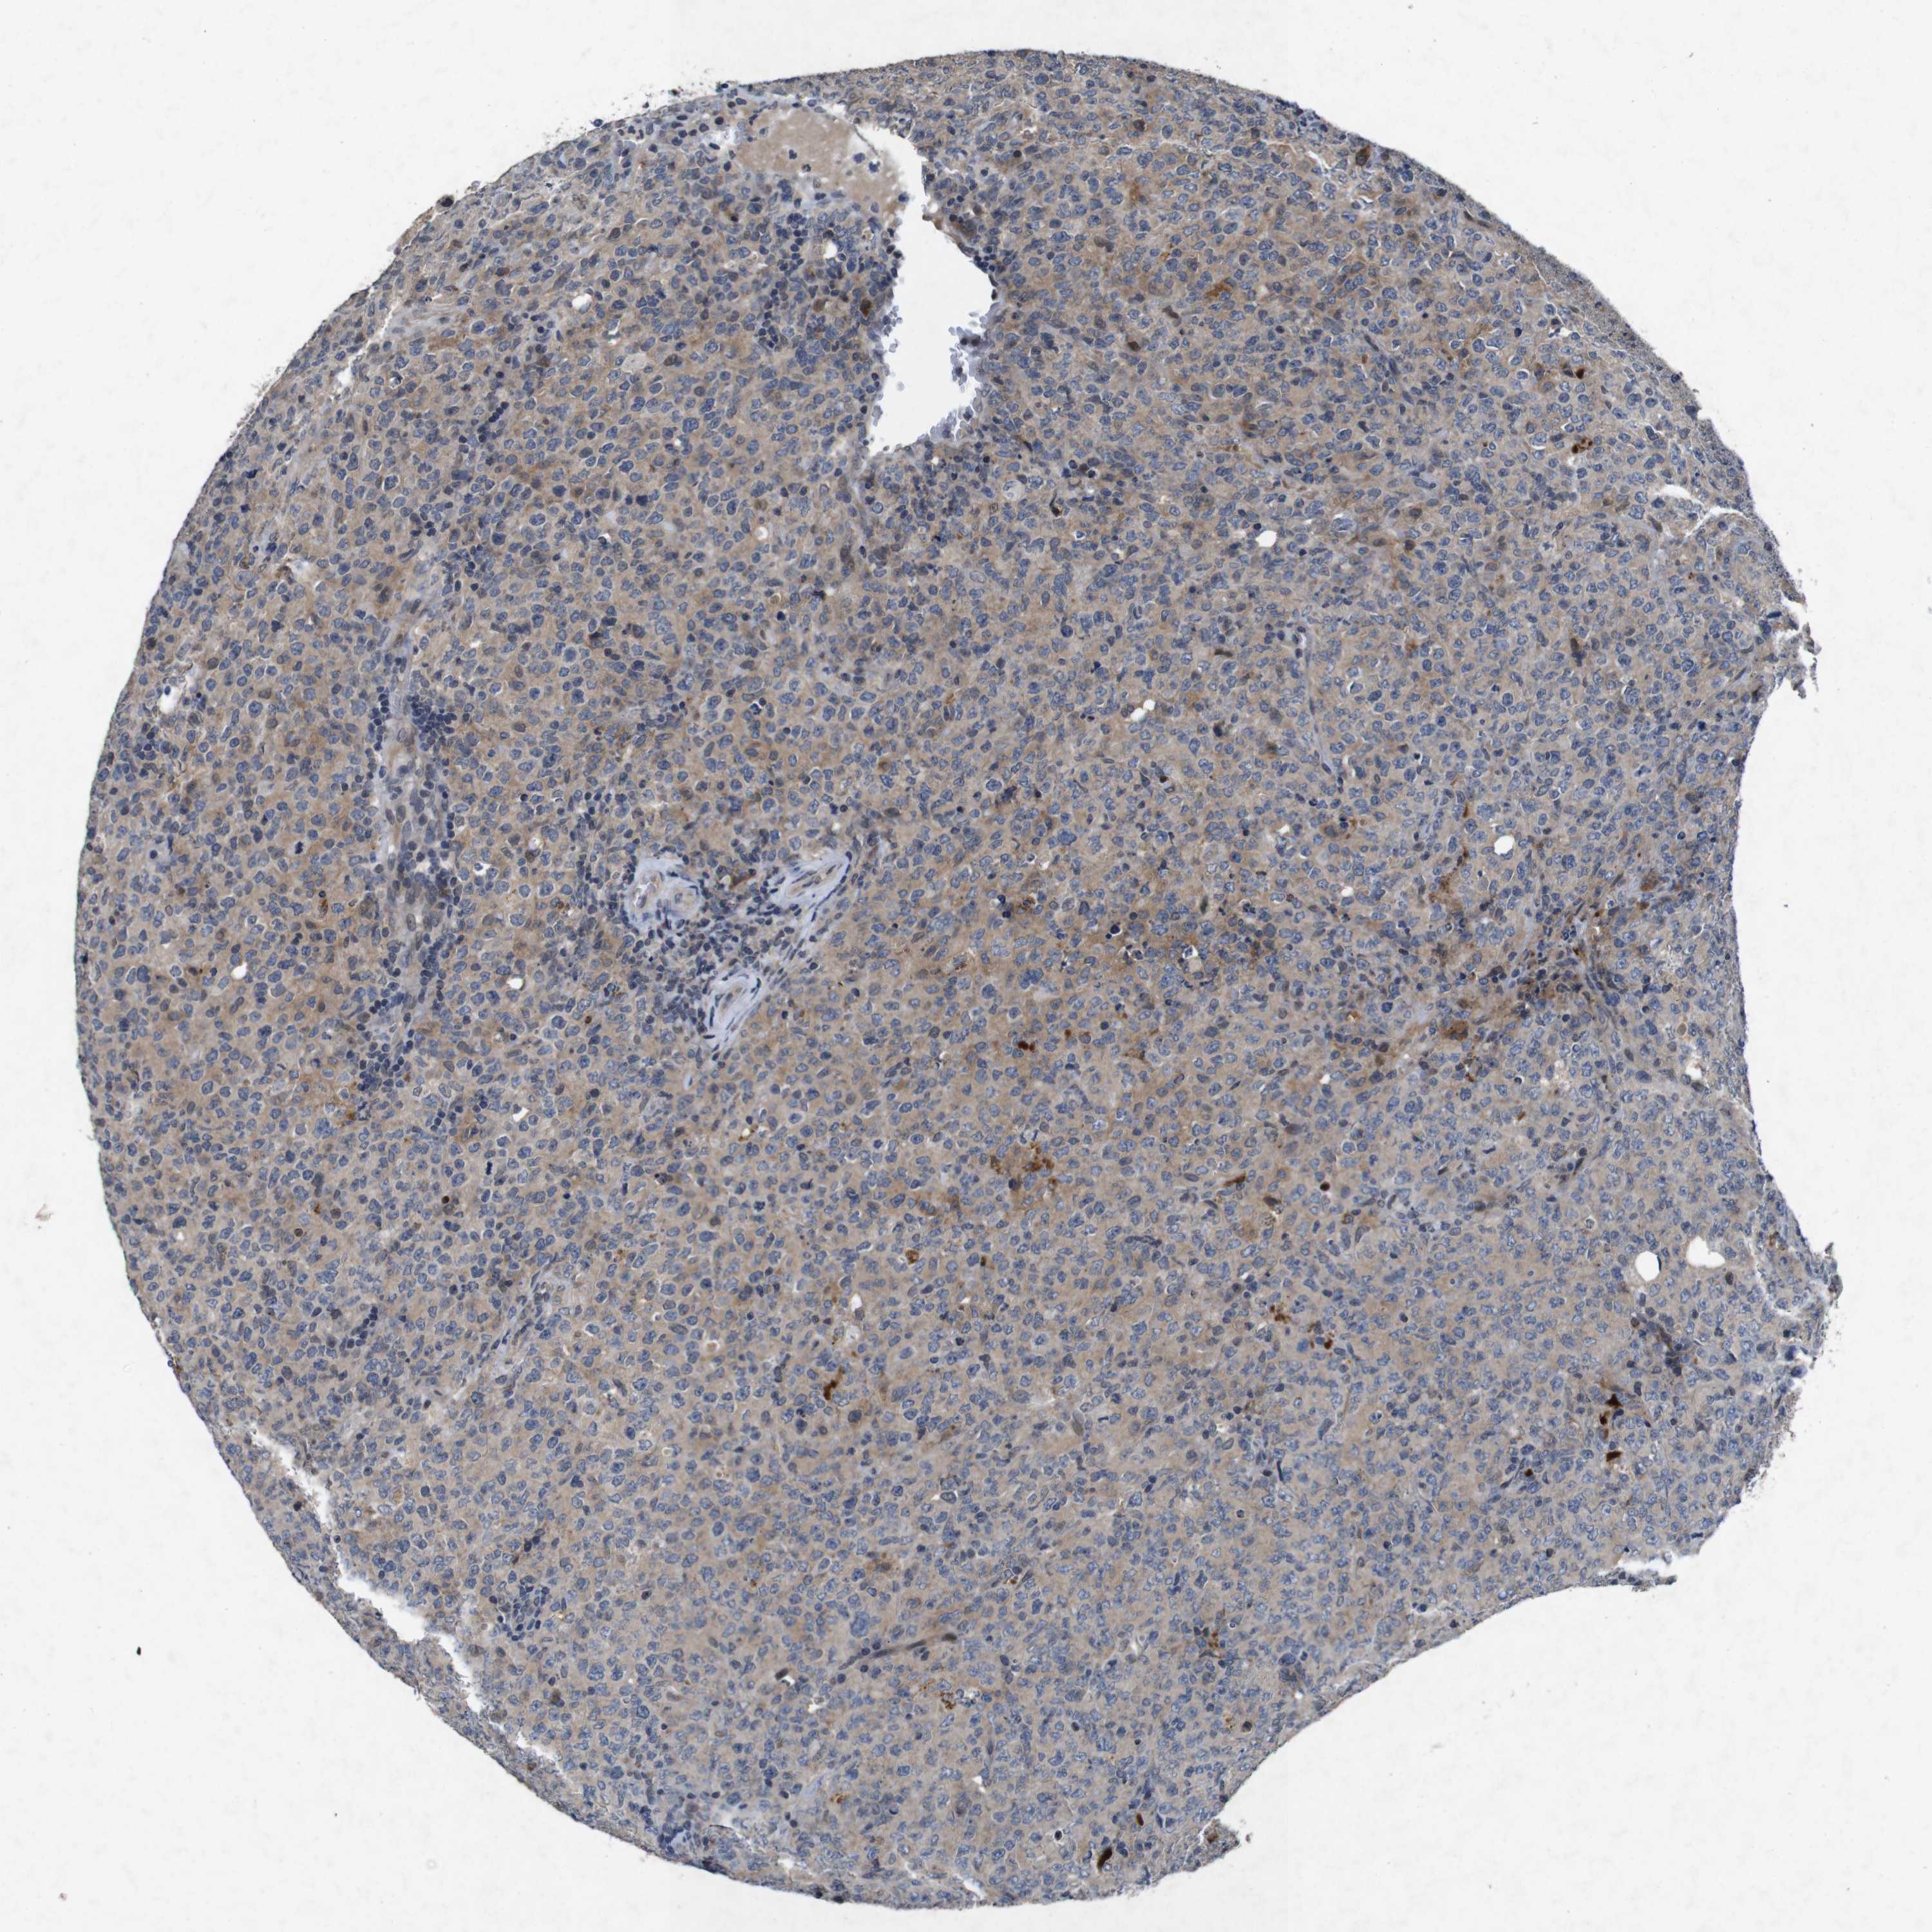

CANCER LYMPHOMA Show tissue menu

LYMPHOMA - Protein expressioni

A mouse-over function shows sample information and annotation data. Click on an image to view it in a full screen mode. Samples can be filtered based on level of antibody staining by selecting one or several of the following categories: high, medium, low and not detected. The assay and annotation is described here.

Antibody stainingi

Antibody staining in the annotated cell types in the current human tissue is reported as not detected, low, medium, or high, based on conventional immunohistochemistry profiling in selected tissues. This score is based on the combination of the staining intensity and fraction of stained cells.

Each image is clickable and will lead to virtual microscopy that enables deeper exploration of all samples and also displays staining intensity scores, fraction scores and subcellular localization as well as patient and tissue information for each sample.

Antibody HPA026441

Antibody CAB013090

Staining

High

Medium

Low

Not detected

Intensity

Strong

Moderate

Weak

Negative

Quantity

>75%

75%-25%

<25%

None

Location

Nuclear

Cytoplasmic/membranous

Cytoplasmic/membranous,nuclear

Hodgkin's disease, NOS

Malignant lymphoma, non-Hodgkin's type, High grade

Malignant lymphoma, non-Hodgkin's type, Low grade